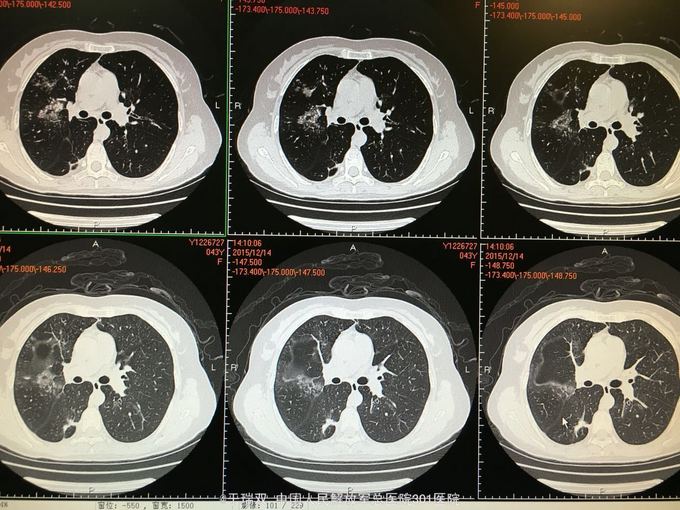

患者中年女女性,2014年10月无明显诱因出现咳嗽咳黄白痰,伴有喘息,自行药物治疗无好转。2014年11月下旬就诊于北京某医院诊断为“变应性支气管肺曲霉病、真菌性肺炎”先后给予伊曲康唑静滴及口服伏立康唑抗真菌、平喘等治疗后症状好转。复查CT炎症也吸收好转,于2015年3月停用以上药物。2015年11月患者再次出现上述症状,胸部CT见右肺班片状实变影,就诊于我院给予左氧氟沙星、西替利秦及化痰止咳治疗后略有好转,遂住院。2015年11月5日CT(图1、2),2015年12月14CT(图3、4、5、6)

肺部感染:变应性支气管肺曲霉菌病?侵袭性肺部曲霉菌病? 氯雷他定抗过敏,两性霉素B雾化吸入,乙酰半胱氨酸雾化,伏立康唑静点0.2,每12小时一次。